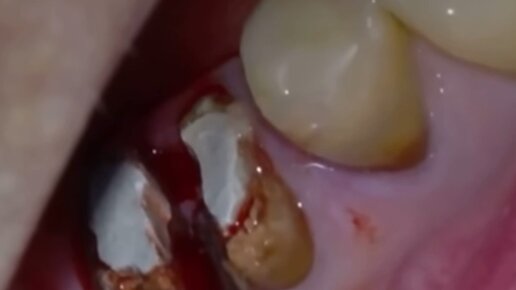

Одномоментная имплантация